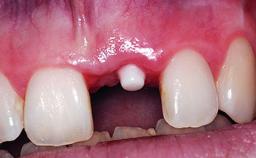

Replacement of a Compromised Upper Right Central Incisor: Hard- and Soft-tissue Augmentation, Late Placement of an RC Bone Level Implant

A 36-year-old male patient with a compromised maxillary central incisor was referred by his general dentist for consultation. The patient’s chief complaints were the gradual debonding of a temporary crown on the right central incisor and unsatisfactory esthetics due to an increasing diastema between the right central and lateral incisors. The patient reported a traumatic event some years previously, when a crown had been placed after root-canal treatment. The referring dentist wanted to provide a new crown restoration, but was concerned about the condition of the residual root. Anamnesis was negative for any other dental or periodontal pathology in the remaining dentition. The patient reported taking no medications: He was a smoker (10 to 15 cigs/day) and had realistic esthetic expectations.